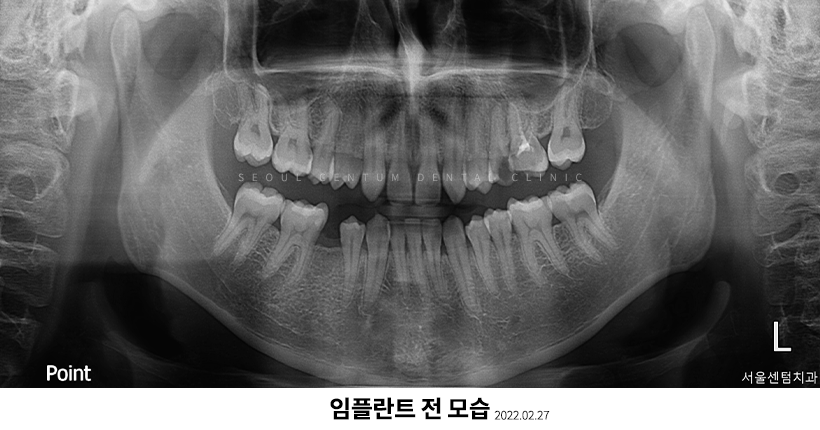

실제로 저희 치과에 내원해 주신 한 환자분의 파노라마 엑스레이 사진입니다.

임플란트는 치아가 없거나 자연치에 손상을 주지 않고 상실된 치아를 회복시키고 싶은 경우 등의 상황에서 진행하면 좋은 술식입니다.

자연치의 기능을 대체해 주기 때문에 치아를 상실했을 때에 비해 생활에서 훨씬 도움이 됩니다.

또한 치관(크라운)을 씌우므로 자연치와 비슷한 외형을 유지할 수 있어 타인이나 자신이 봐도 많이 어색하지 않습니다. 다만 임플란트는 많은 비용과 시간을 필요로 하는 데다가 유지 기간도 길기 때문에 신중히 결정하셔야 합니다.

추가로 임플란트 과정이 1차와 2차 수술로 나눠지기도 하므로 치료 기간이 상이할 수 있는 것인데, 이 부분에 대해서는 잘 모르실 것 같습니다. 그럼 이번에는 임플란트 1차와 더불어 임플란트2차수술과정에 대해 설명드려보겠습니다.